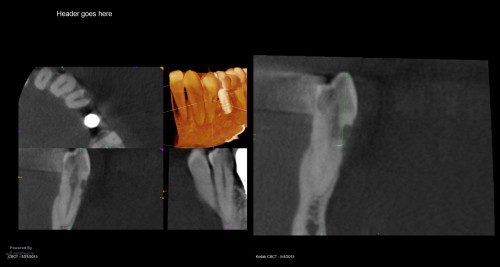

By JK / July 23, 2018

In today for another tooth which I will post under separate cover. CBCT in CH […]